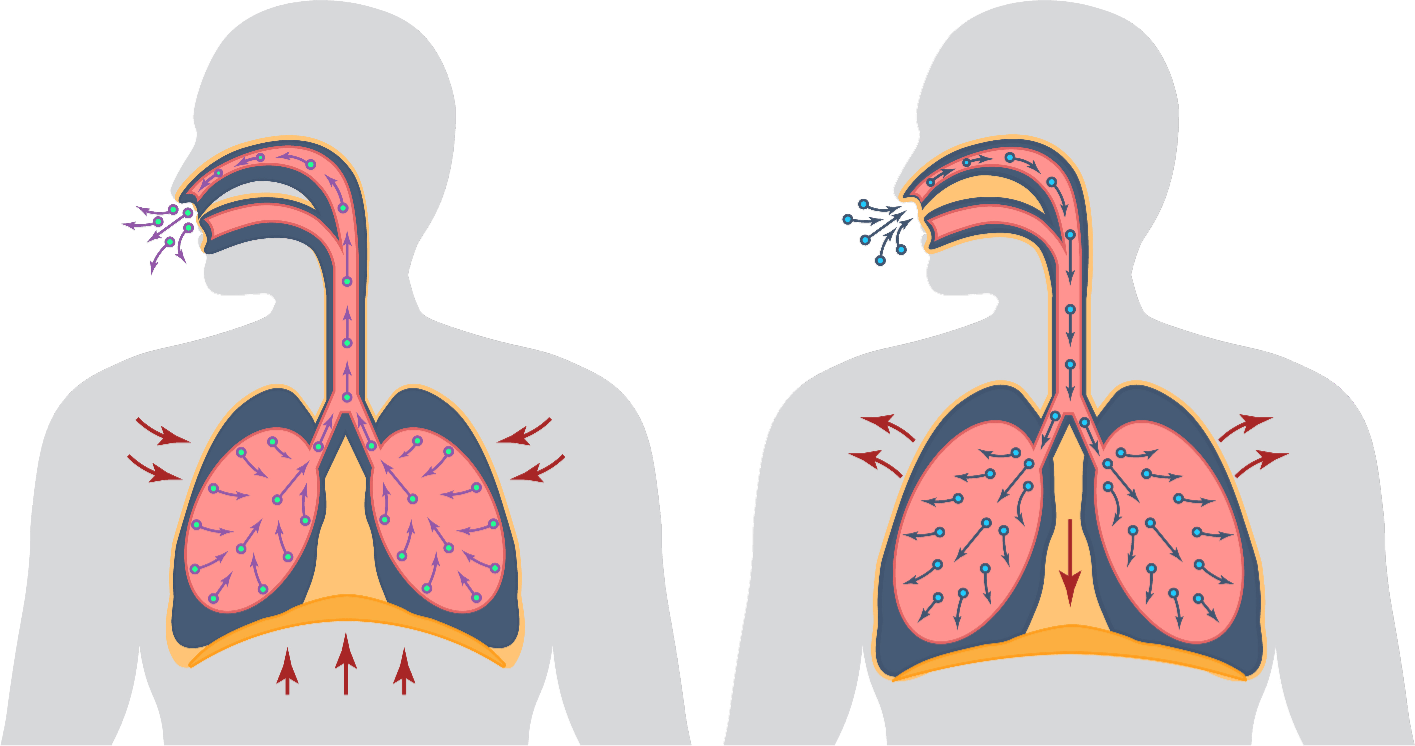

MÉCANISME D’ACTION (MOA)

EA 575MD est également unique pour aider à améliorer les fonctions respiratoires chez les patients souffrant de bronchite.

- L'EA 575MD est un principe actif issu de la feuille de lierre naturelle qui liquéfie le mucus collant piégé dans les voies respiratoires des poumons.

- Il agit alors comme un expectorant, permettant au mucus d'être expulsé plus facilement.

- Lorsque les voies respiratoires se détendent et s'élargissent, le patient peut respirer mieux et plus confortablement.